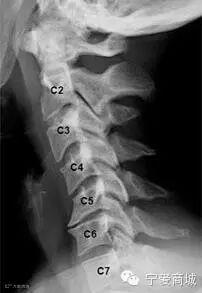

怎样才能知道自己的颈椎是否健康?日常生活中身体发出的小信号会提示不同类型的颈椎问题。

信号一,长时低头伏案工作,感觉到头晕难受,考虑为椎动脉型颈椎病;

信号二,不明原因的肩颈酸痛,手臂发麻,考虑为神经根型颈椎病;

信号三,正常直行走路却常出现“跑偏”问题,考虑为脊髓型颈椎病;

信号四,经常有不明原因的头晕、眼花、耳鸣、手麻、心动过速、心前区疼痛等一系列症状,考虑为交感神经型颈椎病。

如果同时出现上述几类症状,则考虑为混合型颈椎病。